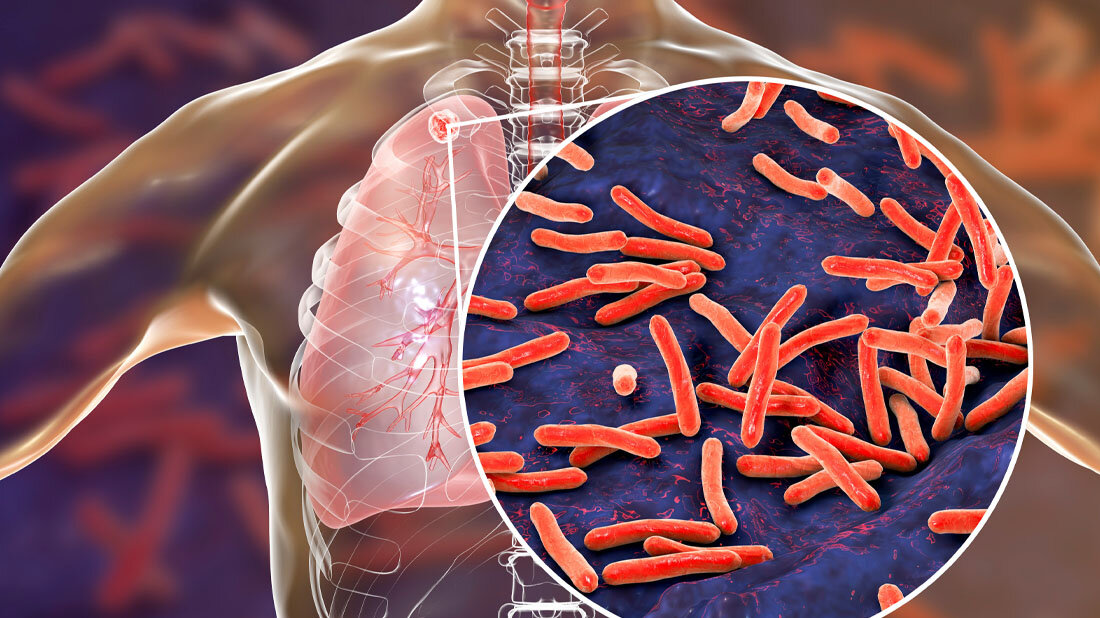

Tuberkulose (TB) ist eine der weltweit häufigsten Infektionskrankheiten mit durchschnittlich sechs Millionen diagnostizierten Infektionen jährlich. Sie stellte vor dem Auftauchen von SARS-CoV-2 die häufigste Todesursache durch einen einzelnen Erreger dar. Vor allem die Multiresistenzen bereiten Sorgen. Prof. Bernd Plietker und seine Arbeitsgruppe an der Professur für Organische Chemie I der TU Dresden haben nun gezielt eine Naturstoffklasse weiterentwickelt – die polyprenylierten polyzyklischen Acylphloroglucinolen (kurz PPAP). Das dabei entstandene Derivat PPAP53 zeichnet sich aufgrund seiner Eigenschaften durch ein großes Potential zur Anwendung im medizinalchemischen Kontext aus. In Zusammenarbeit mit mehreren Forschungseinrichtungen, wie den Universitäten Ulm und Mainz konnte gezeigt werden, dass PPAP53 sehr vielversprechend bei der Bekämpfung multiresistenter Tuberkulose ist und bei neurogenerativen Erkrankungen neue Behandlungsperspektiven eröffnet.

Eine Früherkennung der Infektion durch das Bakterium Mycobacterium tuberculosis (Mtb) ist durch die Nutzung humaner Macrophagen (Fresszellen des Immunsystems) als quasi Wirt zur Vermehrung des Mtb stark erschwert. Aufgrund dieses „Versteckspiels“ des Mtb in den menschlichen Macrophagen greifen übliche Methoden der Diagnostik erst nach dem Kollaps der Macrophagen, man spricht dann von der „offenen Tuberkulose“. Mtb kann durch gängige Antibiotika, die über lange Zeiträume verabreicht werden, behandelt werden, allerdings fördert die wiederholte Exposition von Mycobacterium tuberculosis (Mtb) mit gängigen Antibiotika die Entwicklung multiresistenter und extensiv arzneimittelresistenter Stämme.